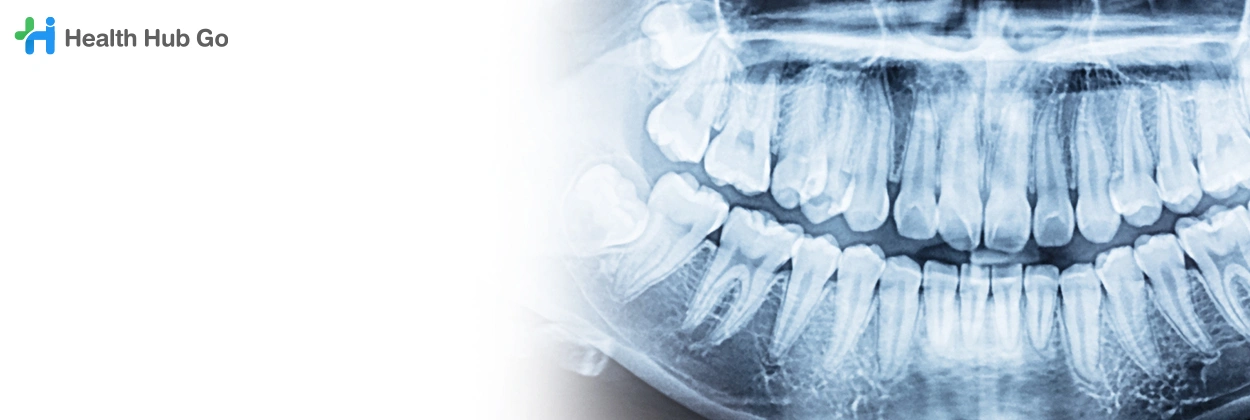

เอกซเรย์ฟันกรามด้านใน

Bitewing Dental X-ray